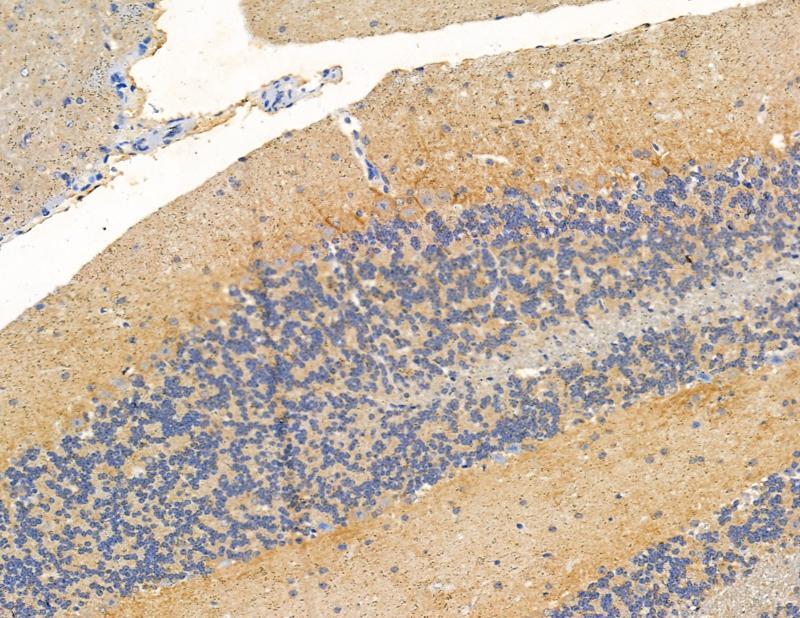

- Submitted by

- Invitrogen Antibodies (provider)

- Main image

- Experimental details

- Immunohistochemistry analysis of RASA4 in mouse brain tissue. The sample was formaldehyde fixed and a heat mediated antigen retrieval step in citrate buffer was performed. Samples were incubated with RASA4 polyclonal antibody (Product # PA5-115826) using a dilution of 1:100 (4°C overnight) followed by HRP conjugated anti-Rabbit secondary antibody.